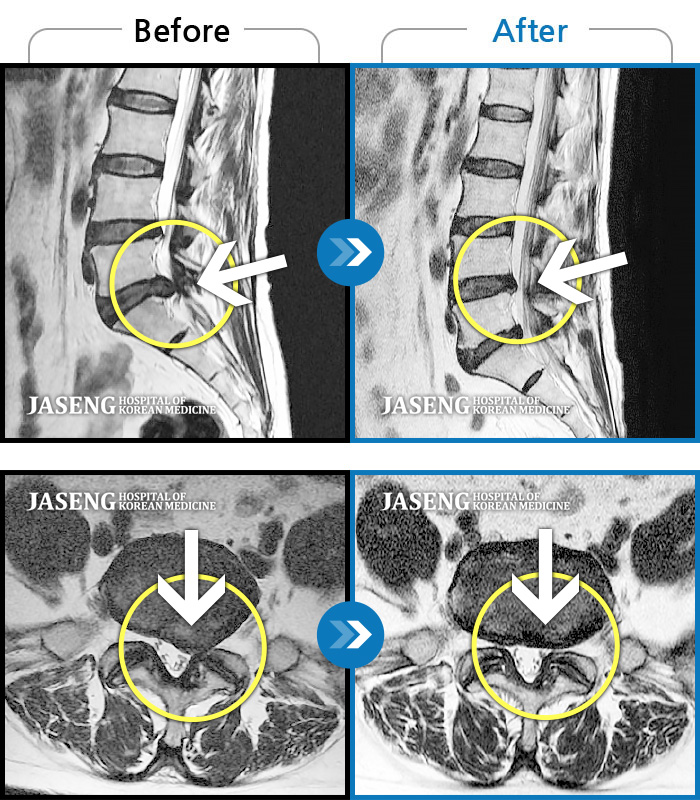

처음 내원시 허리 통증이 심하여 일상생활에 불편감이 있으신 환자분이셨습니다.

2023.10.03 ~ 2025.03.22